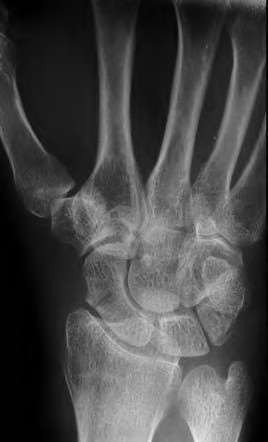

A 35-year-old woman reports wrist pain after a fall onto an outstretched hand. On exam, she has focal tenderness over the wrist snuffbox. A radiograph and CT image are shown in Figures A and B. What is the proper treatment of her injury?